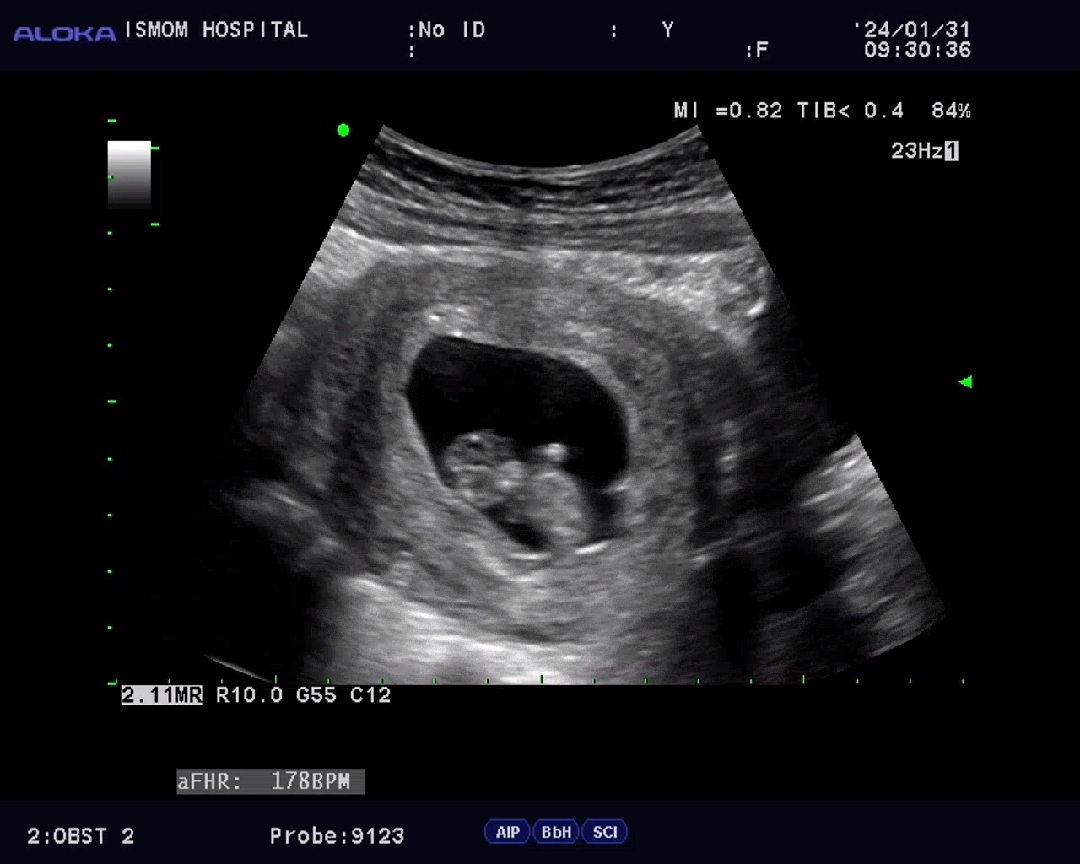

9월2일예정이에요ㅎㅎ 빠르게자라네요 벌써3cm! 심소듣고있는데 갑자기 꼬물거려서 선생님이랑 한 5초?동안 가만히 보고있으니 엉덩이를 씰룩씰룩 하더라고요ㅋㅋㅋ 그동안 초음파볼때는 잘 있구나~정도였는데 움직이는걸 보니 살짝 눙물이ㅠㅠ 나더라고요. 내시키 엄마왔다고 꼬물거리는거 같기도 하고ㅋㅋ 설끝나고 갈 예정인데 요즘은 검진날만 기다려지네요ㅎㅎ